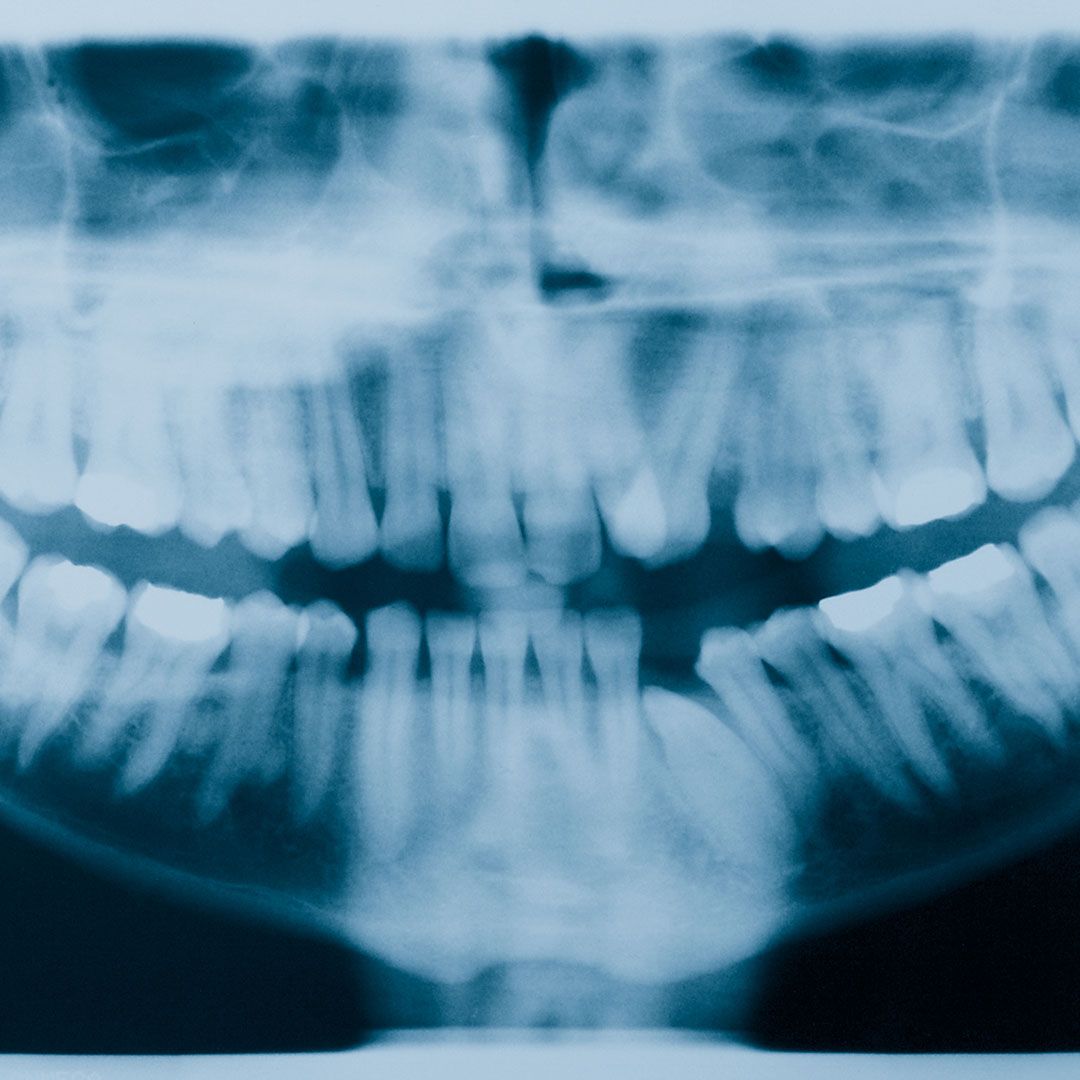

Dental crowns are placed over a damaged or decayed tooth to protect it from further harm and restore its natural shape and appearance. Our team uses the latest in aesthetic dentistry techniques to create crowns that blend seamlessly with your existing teeth for a smile that's as natural as can be.

When one or more teeth are missing, dental bridges come to the rescue! These restorative devices use the surrounding teeth for support and fill in the gap with a replacement tooth. Bridges not only improve your smile, but they also prevent your remaining teeth from shifting out of place.

At Boulder Smiles, we believe in utilizing the latest technology and techniques in dental restoration. With the help of digital imagery and 3D printing, we can create precise and personalized dental crowns and bridges that will last a lifetime.